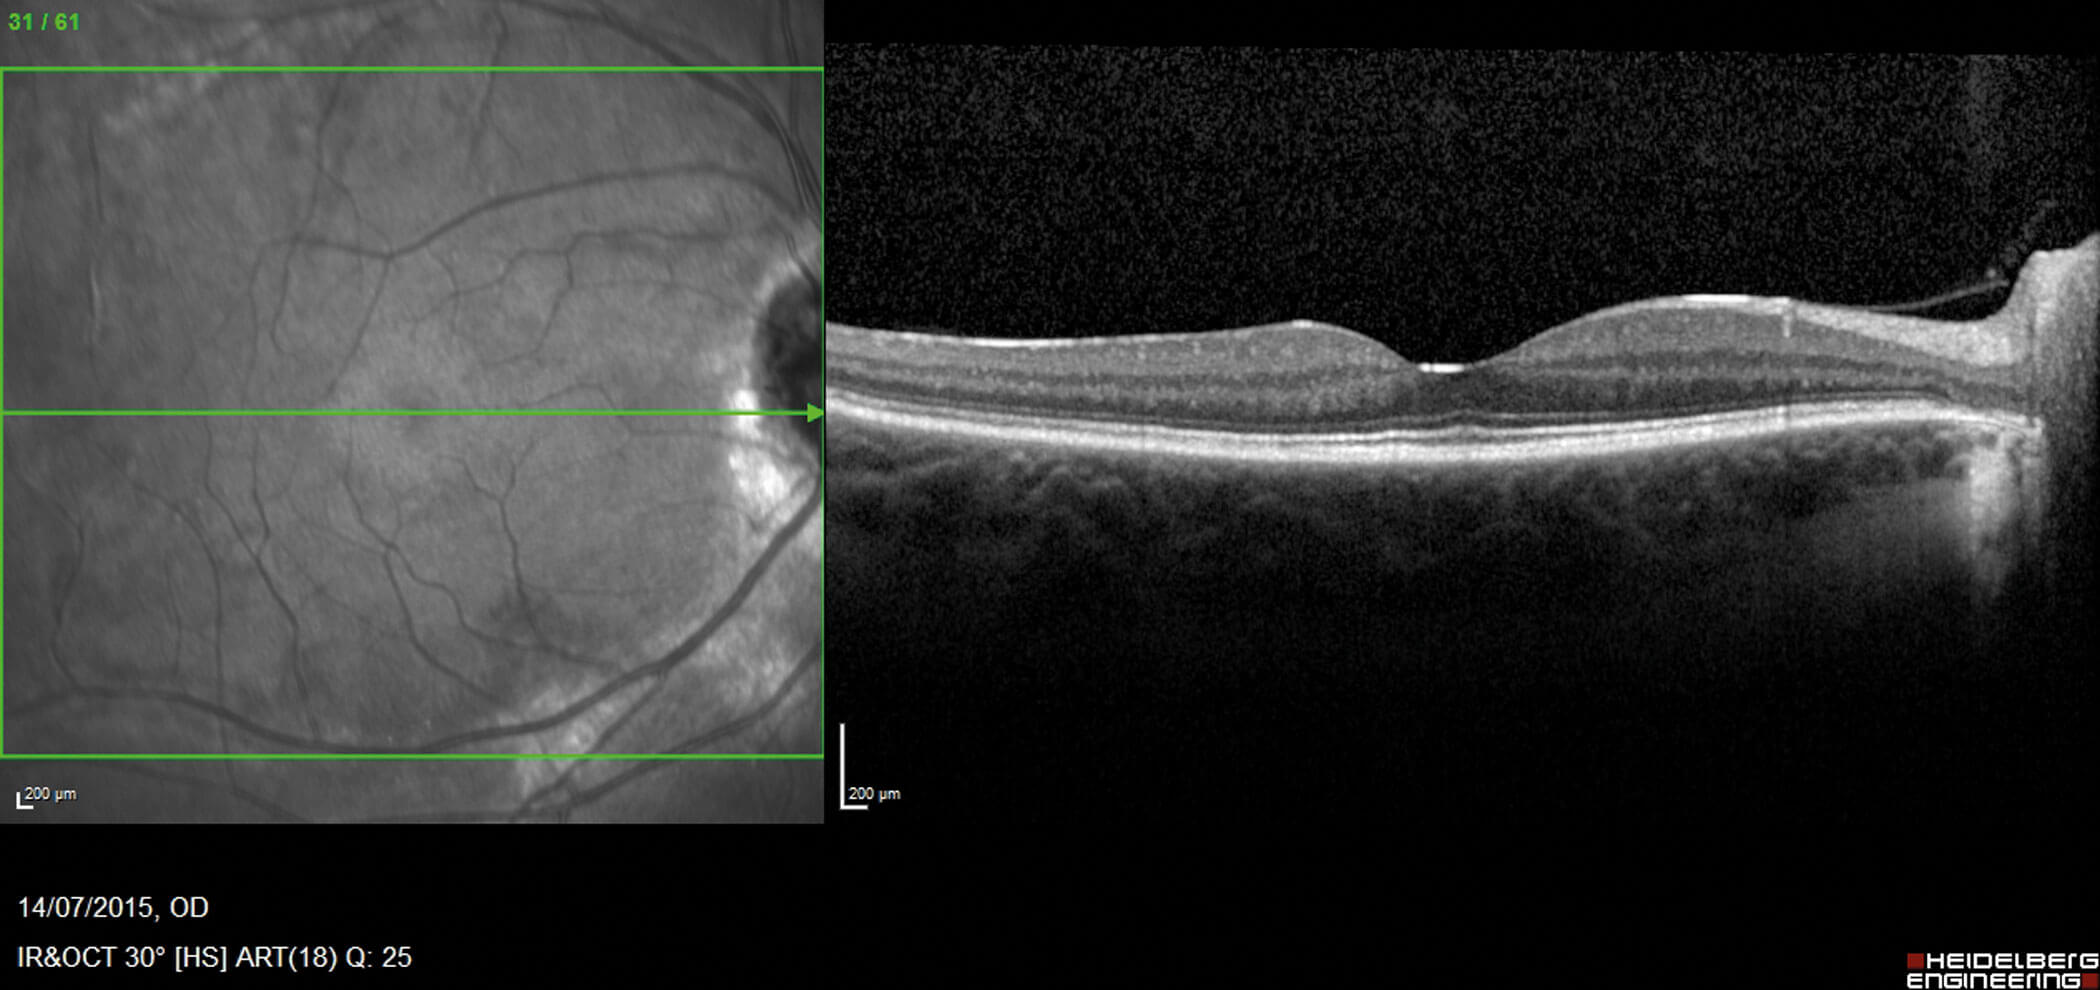

Figures 4a and 4b: Macula OCT demonstrating normal anatomy at the central macula and fovea.

Her fundus appearances remained largely unchanged over three years aside from a slight increase in pigment deposition within the same distribution. Her visual acuity remained excellent at 6/6 or better in both eyes at each visit. The visual field remained stable or only very slowly progressive. Macula OCT at each visit remained stable and dry.

In human eyes, descriptions of histopathological change are based on multimodal imaging techniques including spectral-domain-OCT (SD-OCT) and fluorescein angiography (FFA), as well as visual electrophysiology. In a retrospective study by Lee, et al., SD-OCT imaging of retinochoroidal atrophic areas in PPRCA showed thinning of the outer nuclear layer (ONL), external limiting membrane (ELM), ellipsoid zone (EZ) and interdigitation zone (IZ) band. Reduced choroidal thickness is another feature even in the absence of RPE atrophy. Pigmented paravenous retinochoroidal atrophy also appears to primarily affect choroidal vasculature as evidenced by findings in keeping with choriocapillaris hypoperfusion on OCT angiography, with relative sparing of the retinal capillary plexuses [12]. Macula may be involved and this is characterised by disruptions of the EZ, IZ, and RPE, as well as choroidal thinning [10,12].

Optical coherence tomography

Optical coherence tomography findings include absent EZ and ELM, thinning of ONL and outer plexiform layer, partial preservation of RPE, and choroidal thinning. Retinal nerve fibre layer and GCL can also be thin, and in cases with macular atrophy, thinning of all retinal layers may be present [17]. Pigment clumps appear as hyper-reflective plaques with underlying shadowing [15]. Optical coherence tomography angiography findings are characterised by vascular impairment, especially at the level of deep capillary plexus [17].